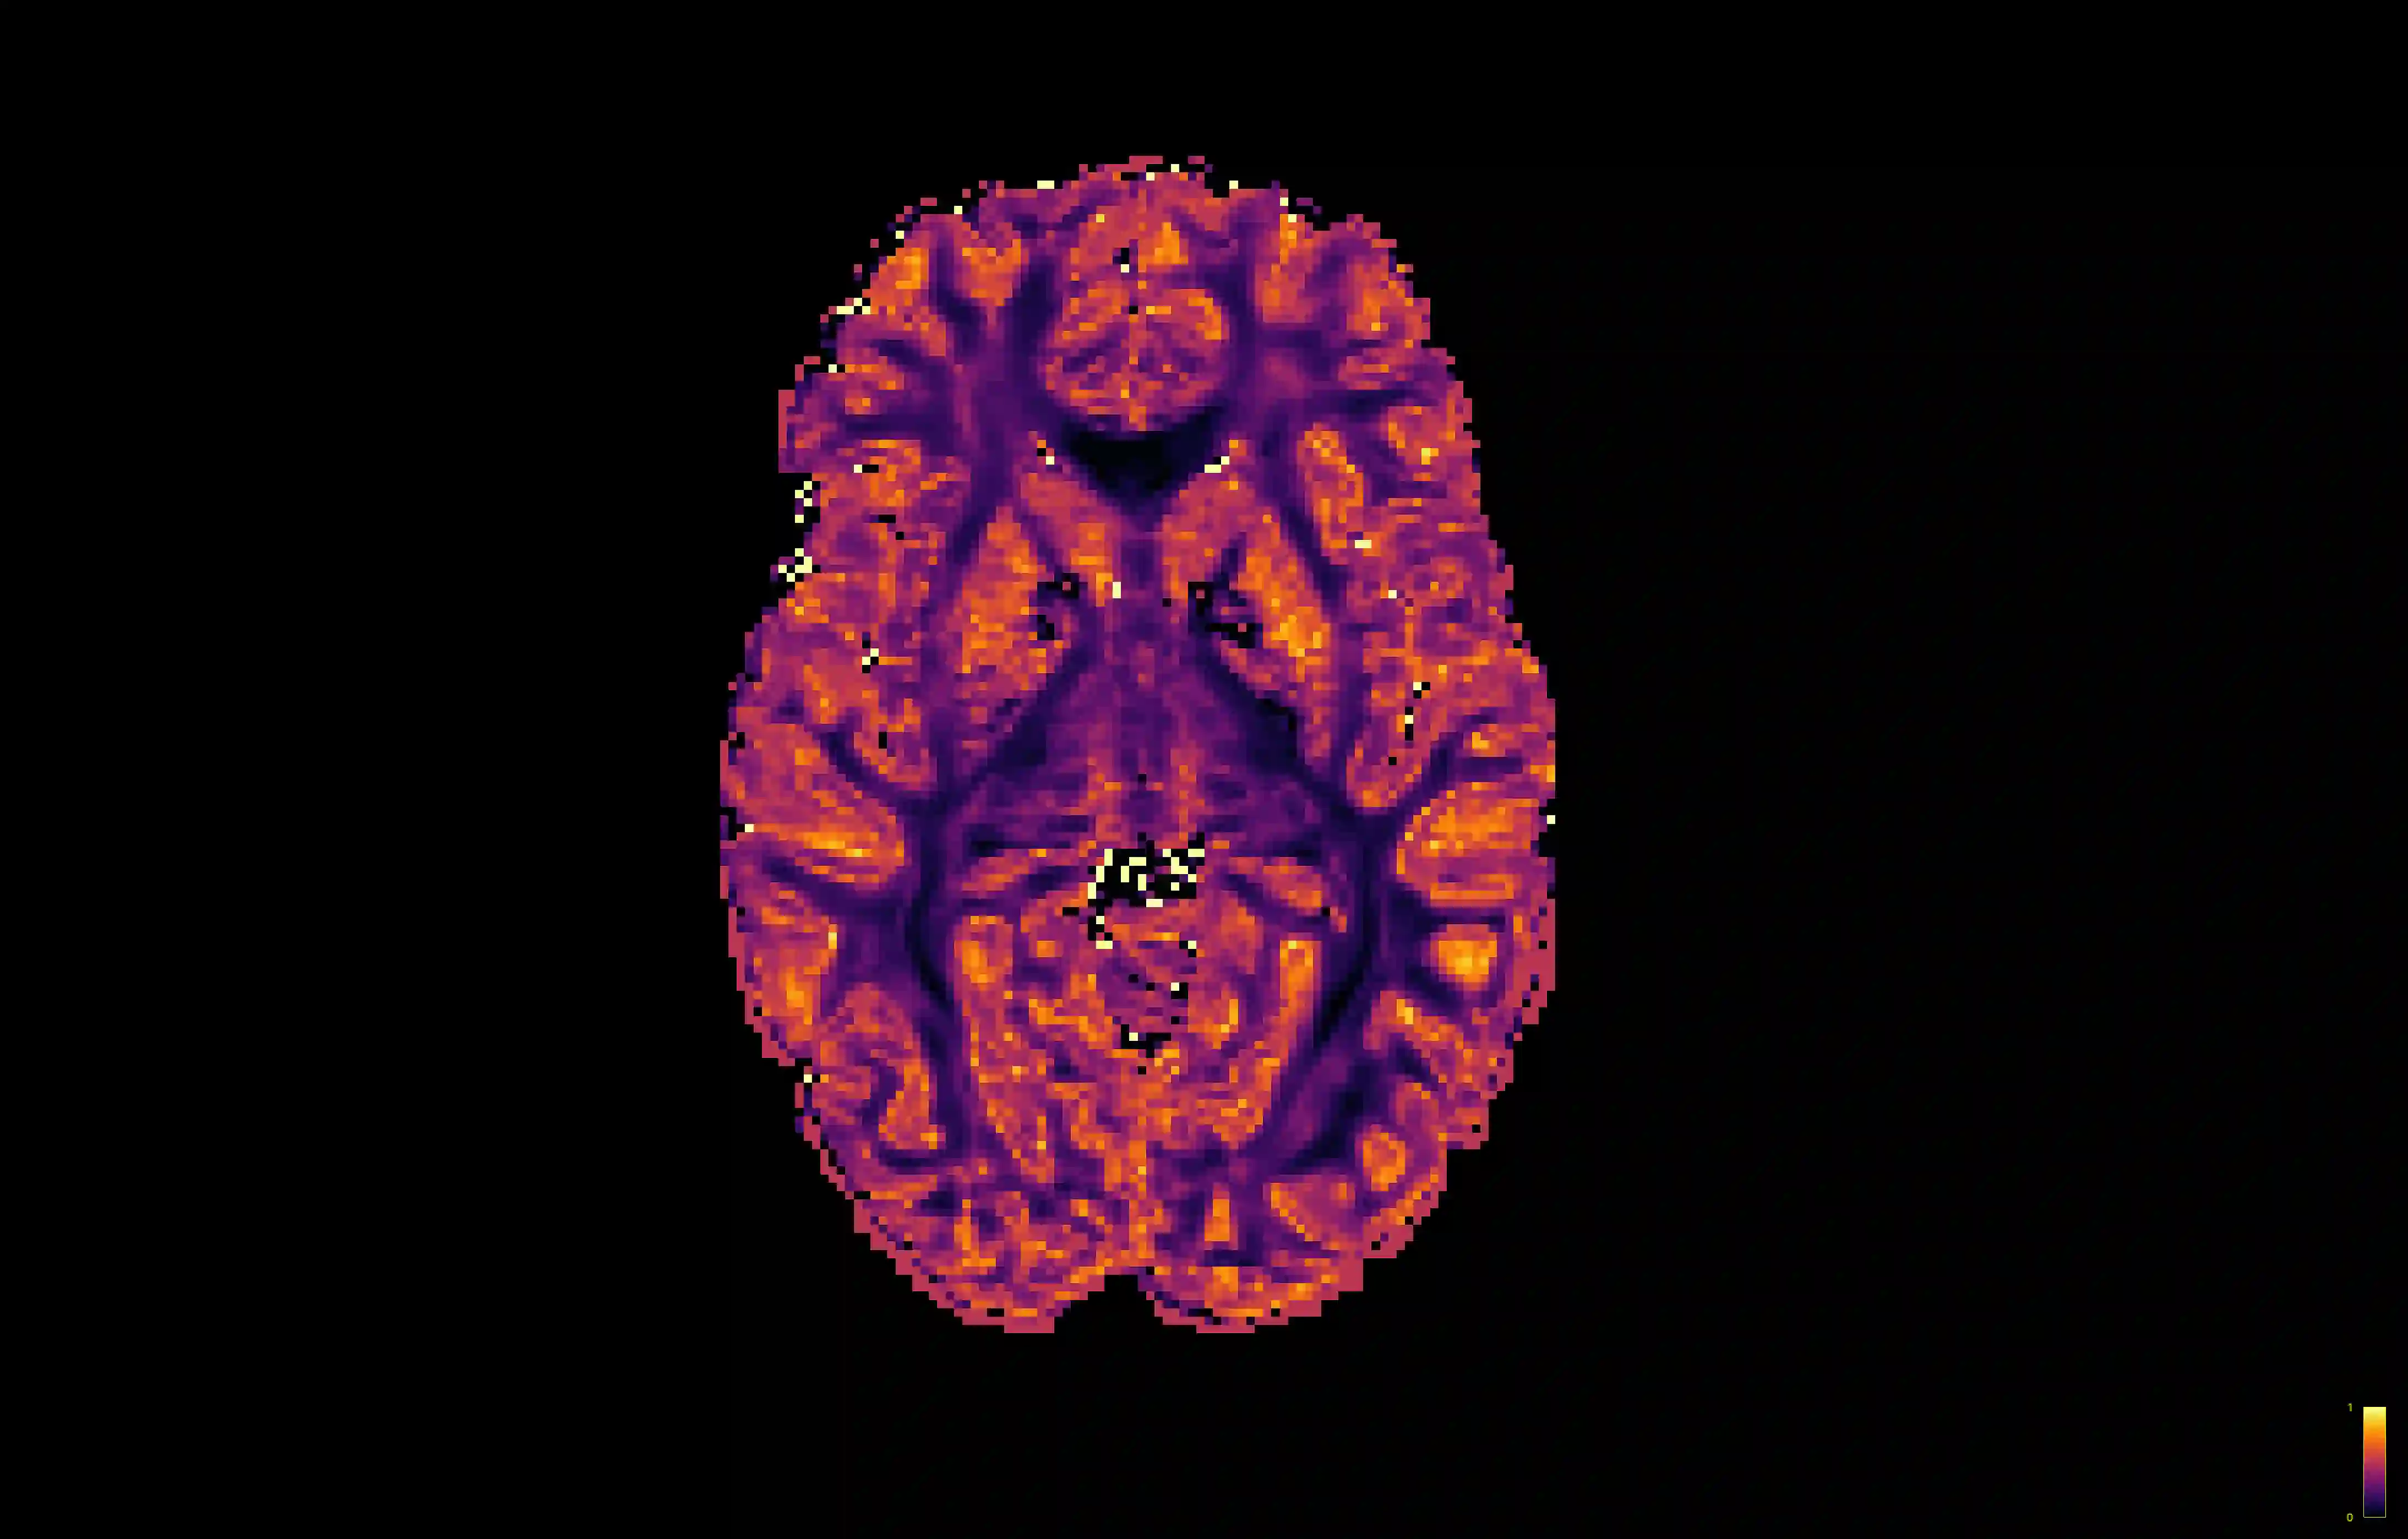

Diffusion MRI (dMRI) is a widely used imaging modality, but requires long scanning times to acquire high resolution datasets. By leveraging the unique geometry present within this domain, we present a novel approach to dMRI angular super-resolution that extends upon the parametric continuous convolution (PCConv) framework. We introduce several additions to the operation including a Fourier feature mapping, global coordinates, and domain specific context. Using this framework, we build a fully parametric continuous convolution network (PCCNN) and compare against existing models. We demonstrate the PCCNN performs competitively while using significantly less parameters. Moreover, we show that this formulation generalises well to clinically relevant downstream analyses such as fixel-based analysis, and neurite orientation dispersion and density imaging.